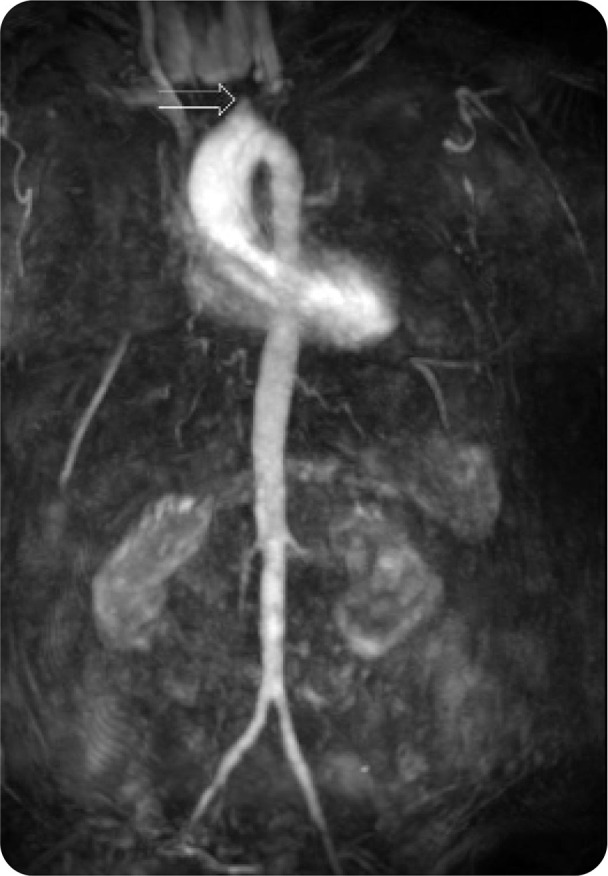

Abstract Image